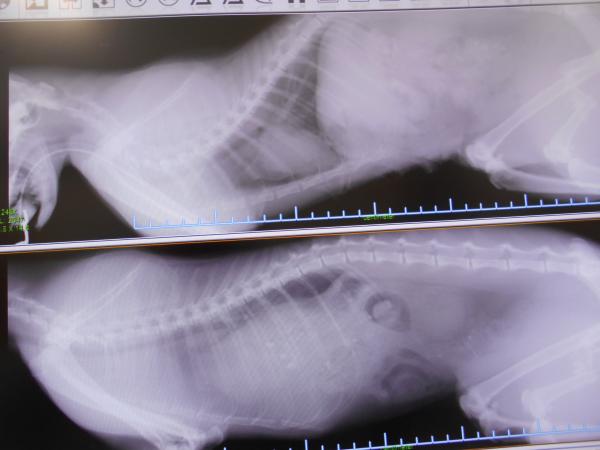

12月29日に交通事故で受傷した猫ちゃんが来院し、

横隔膜ヘルニアの緊急手術を行いました。

大腿骨も骨折していますが、命にかかわるヘルニアの手術を優先して

骨折はケージレストでの治療を考えています。